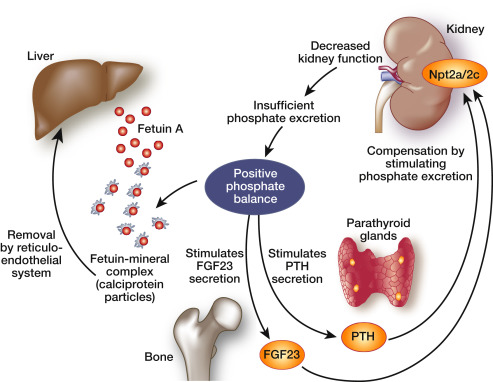

2-5ci mərhələ xroniki böyrək xəstəliyi olan və dializ alan uşaqların yerli vitamin D müalicəsi üçün kliniki təcrübə tövsiyələri